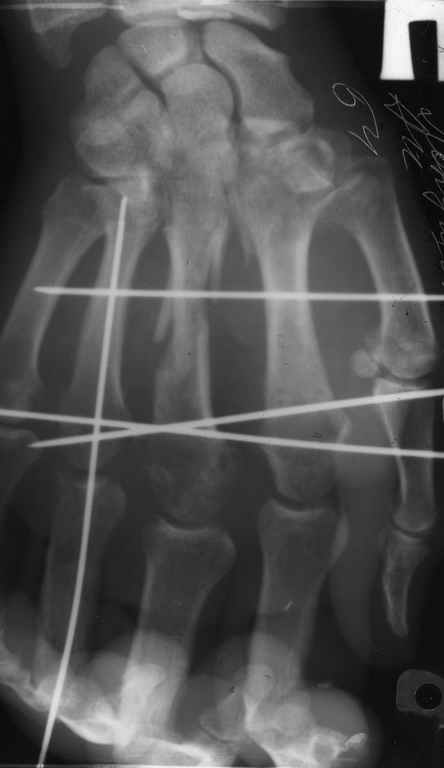

Диагноз на 15.07.05: Стойкая смешанная дермотеногенная контрактура 3,4 пальца правой кисти 3 степени.

-- удалить спицы;

-- сделать рентгенограмму;

Диагноз: Стойкая Смешанная дермотеногенная контрактура 3,4 пальца правой кисти.

Судя по выписному эпикризу, рентгенограммам и фотографиям, пациенту

показано этапное лечение.

Зачем спица в 4 Пястной кости?